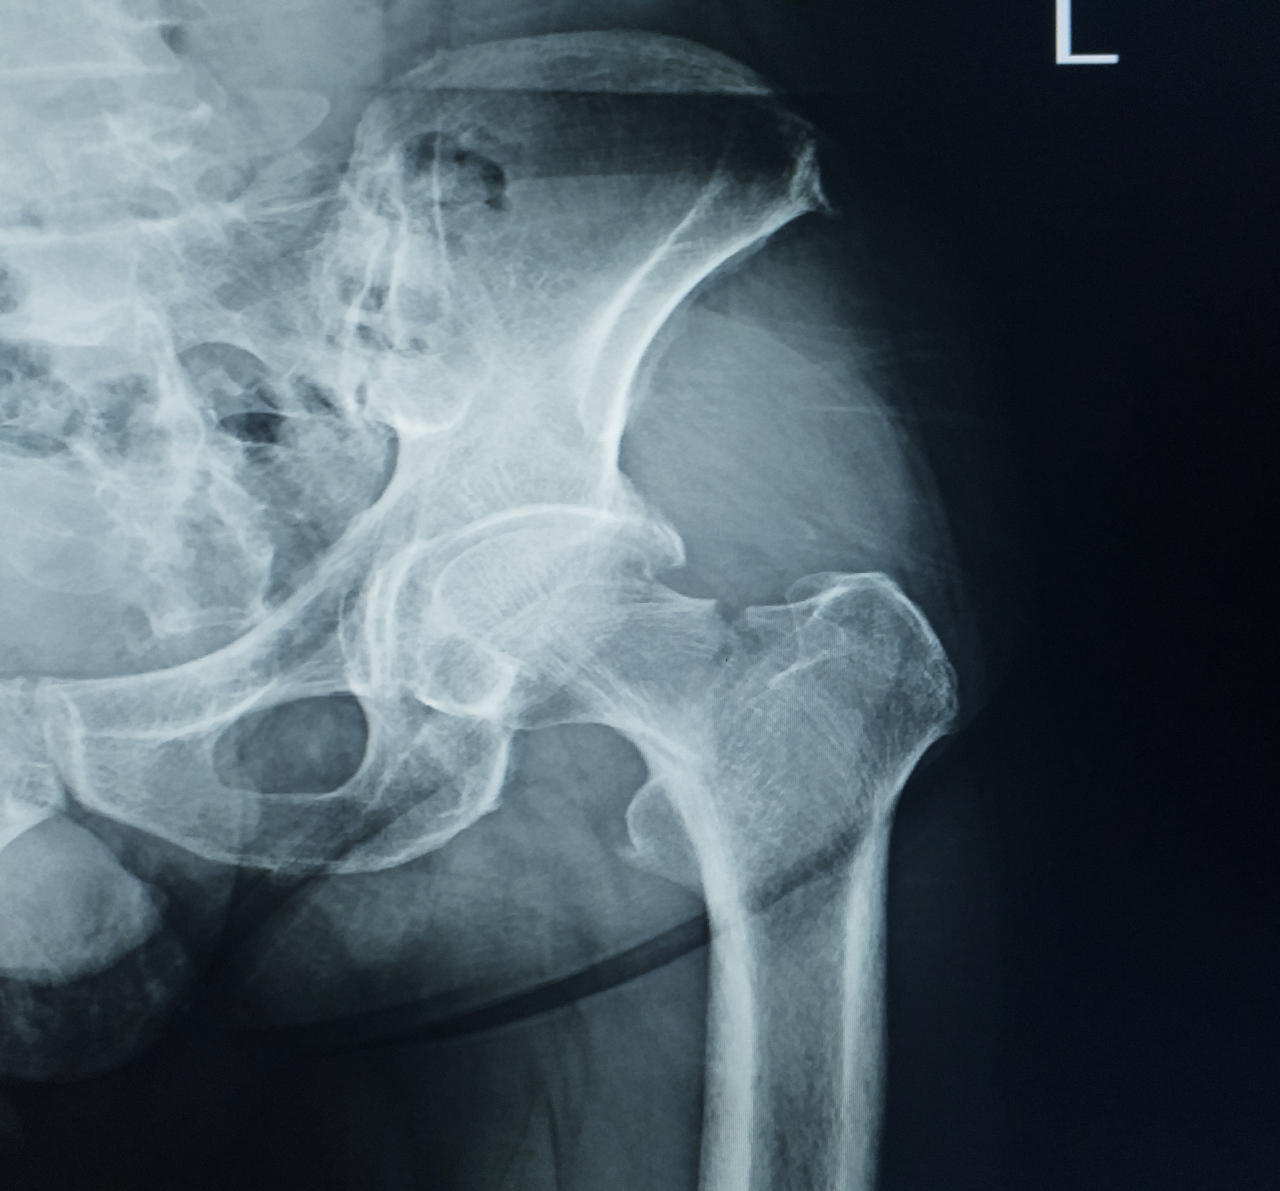

I distretti corporei maggiormente coinvolti sono: anche, colonna vertebrale, polsi, spalle e femore. Da notare che una frattura al femore, può condurre il soggetto colpito a una condizione di disabilità fisica.

La frattura al femore è il caso più drammatico di osteoporosi severa. Essa è indice del fatto che l’osteoporosi ha alterato in maniera significativa la resistenza del nostro tessuto scheletrico aumentando la fragilità ossea portando a questo evento traumatico.

Le sue conseguenze sono una diminuzione della densità minerale ossea e un aumento della fragilità e debolezza dell’apparato scheletrico con predisposizione alla comparsa di fratture al collo del femore, al femore, ai corpi vertebrali, all’avambraccio e alla parte prossimale vicino alla spalla per quanto concerne la frattura dell’omero.

Spesso chi ha avuto fratture al femore presenta fratture vertebrali senza saperlo. I Pazienti che hanno subito una frattura al collo del femore, presentano in oltre il 50% dei casi, anche delle fratture vertebrali.

Una frattura al femore può anche ridurre il soggetto colpito in condizioni di disabilità fisica nel 20% – 30% dei casi.

Dove si riscontrano le fratture da osteoporosi

- all’estremità prossimale del femore, in zona inguinale;

- alle anche, intorno al bacino.

Attenzione: perché il femore può subire ulteriori fratture dopo la prima: nei successivi 5 anni dalla prima frattura le probabilità di subirne una nuova salgono al 20%. E le possibilità che venga colpito da frattura il femore della gamba opposta salgono al 50%. Spesso la frattura al femore può richiedere una lunga degenza.

Le persone che hanno subito una frattura al femore prossimale presentano un tasso di mortalità del 15% – 30% entro un anno dalla frattura.

Il femore è l’osso più lungo e resistente dello scheletro. È situato fra l’anca e il ginocchio e vi si inseriscono molti muscoli fondamentali per il movimento della gamba.

La sua resistenza può però ridursi con l’invecchiamento e può fratturarsi a livello del collo per minimi traumi o anche in loro assenza.